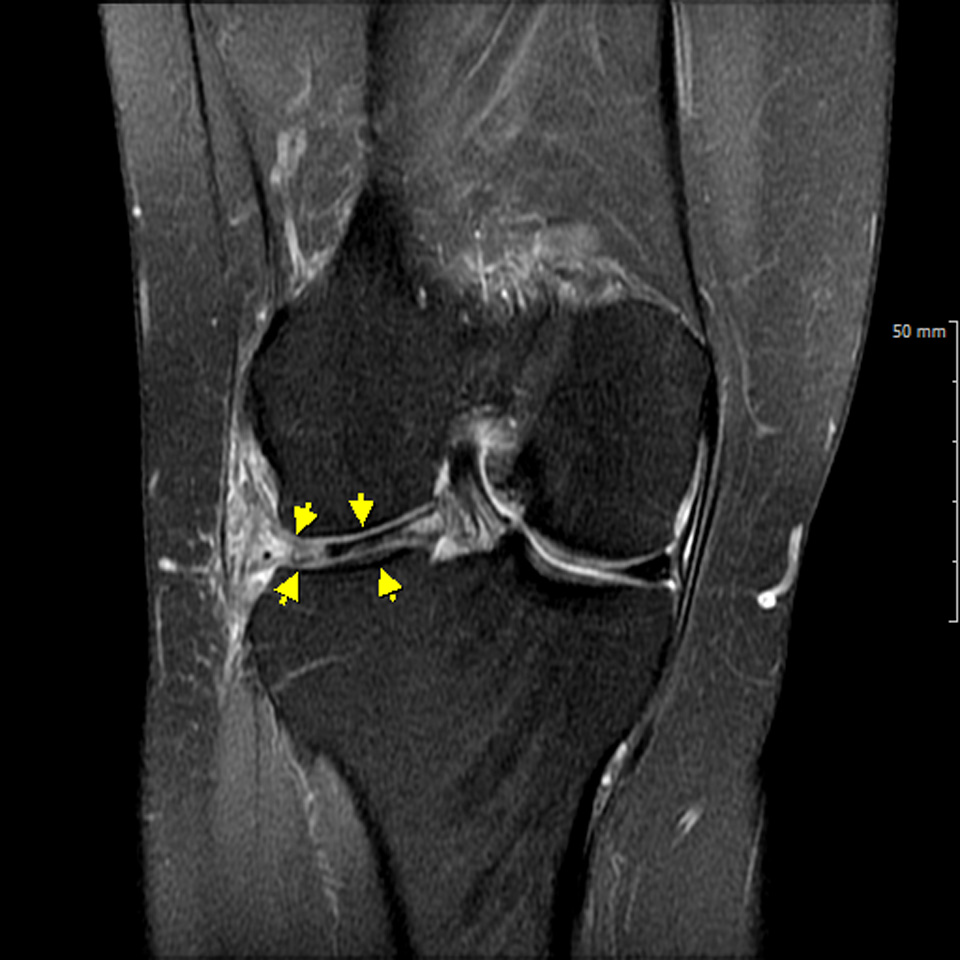

수술전 MRI 소견으로 전방십자인대가 대퇴골부착 부위에서 파열되어 떨어진 소견을 확인할 수 있다.

- 환자 동의하에 게시된 이미지입니다.